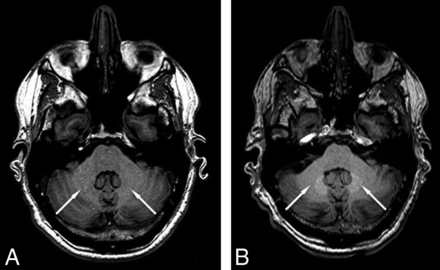

Consistent with expectations, a significant signal intensity increase was detected in the DN/pons ratio by the seventh examination in the linear agent group (t = 4.215, P < .001; Table 1). A sample pair of images showing the signal increase is shown in Fig 4. No significant change was demonstrated in the group receiving gadobutrol (t = −1.422, P = .08; Table 1). The difference between the signal changes seen in these 2 groups was also significant (+3.10% for those receiving linear GBCA; −0.8% for patients receiving gadobutrol; P < .0001; Fig 5 and Table 2).

Sample images showing obvious signal increase, indicated by arrows, after 6 injections of linear GBCAs (B) compared with the baseline scan (A).